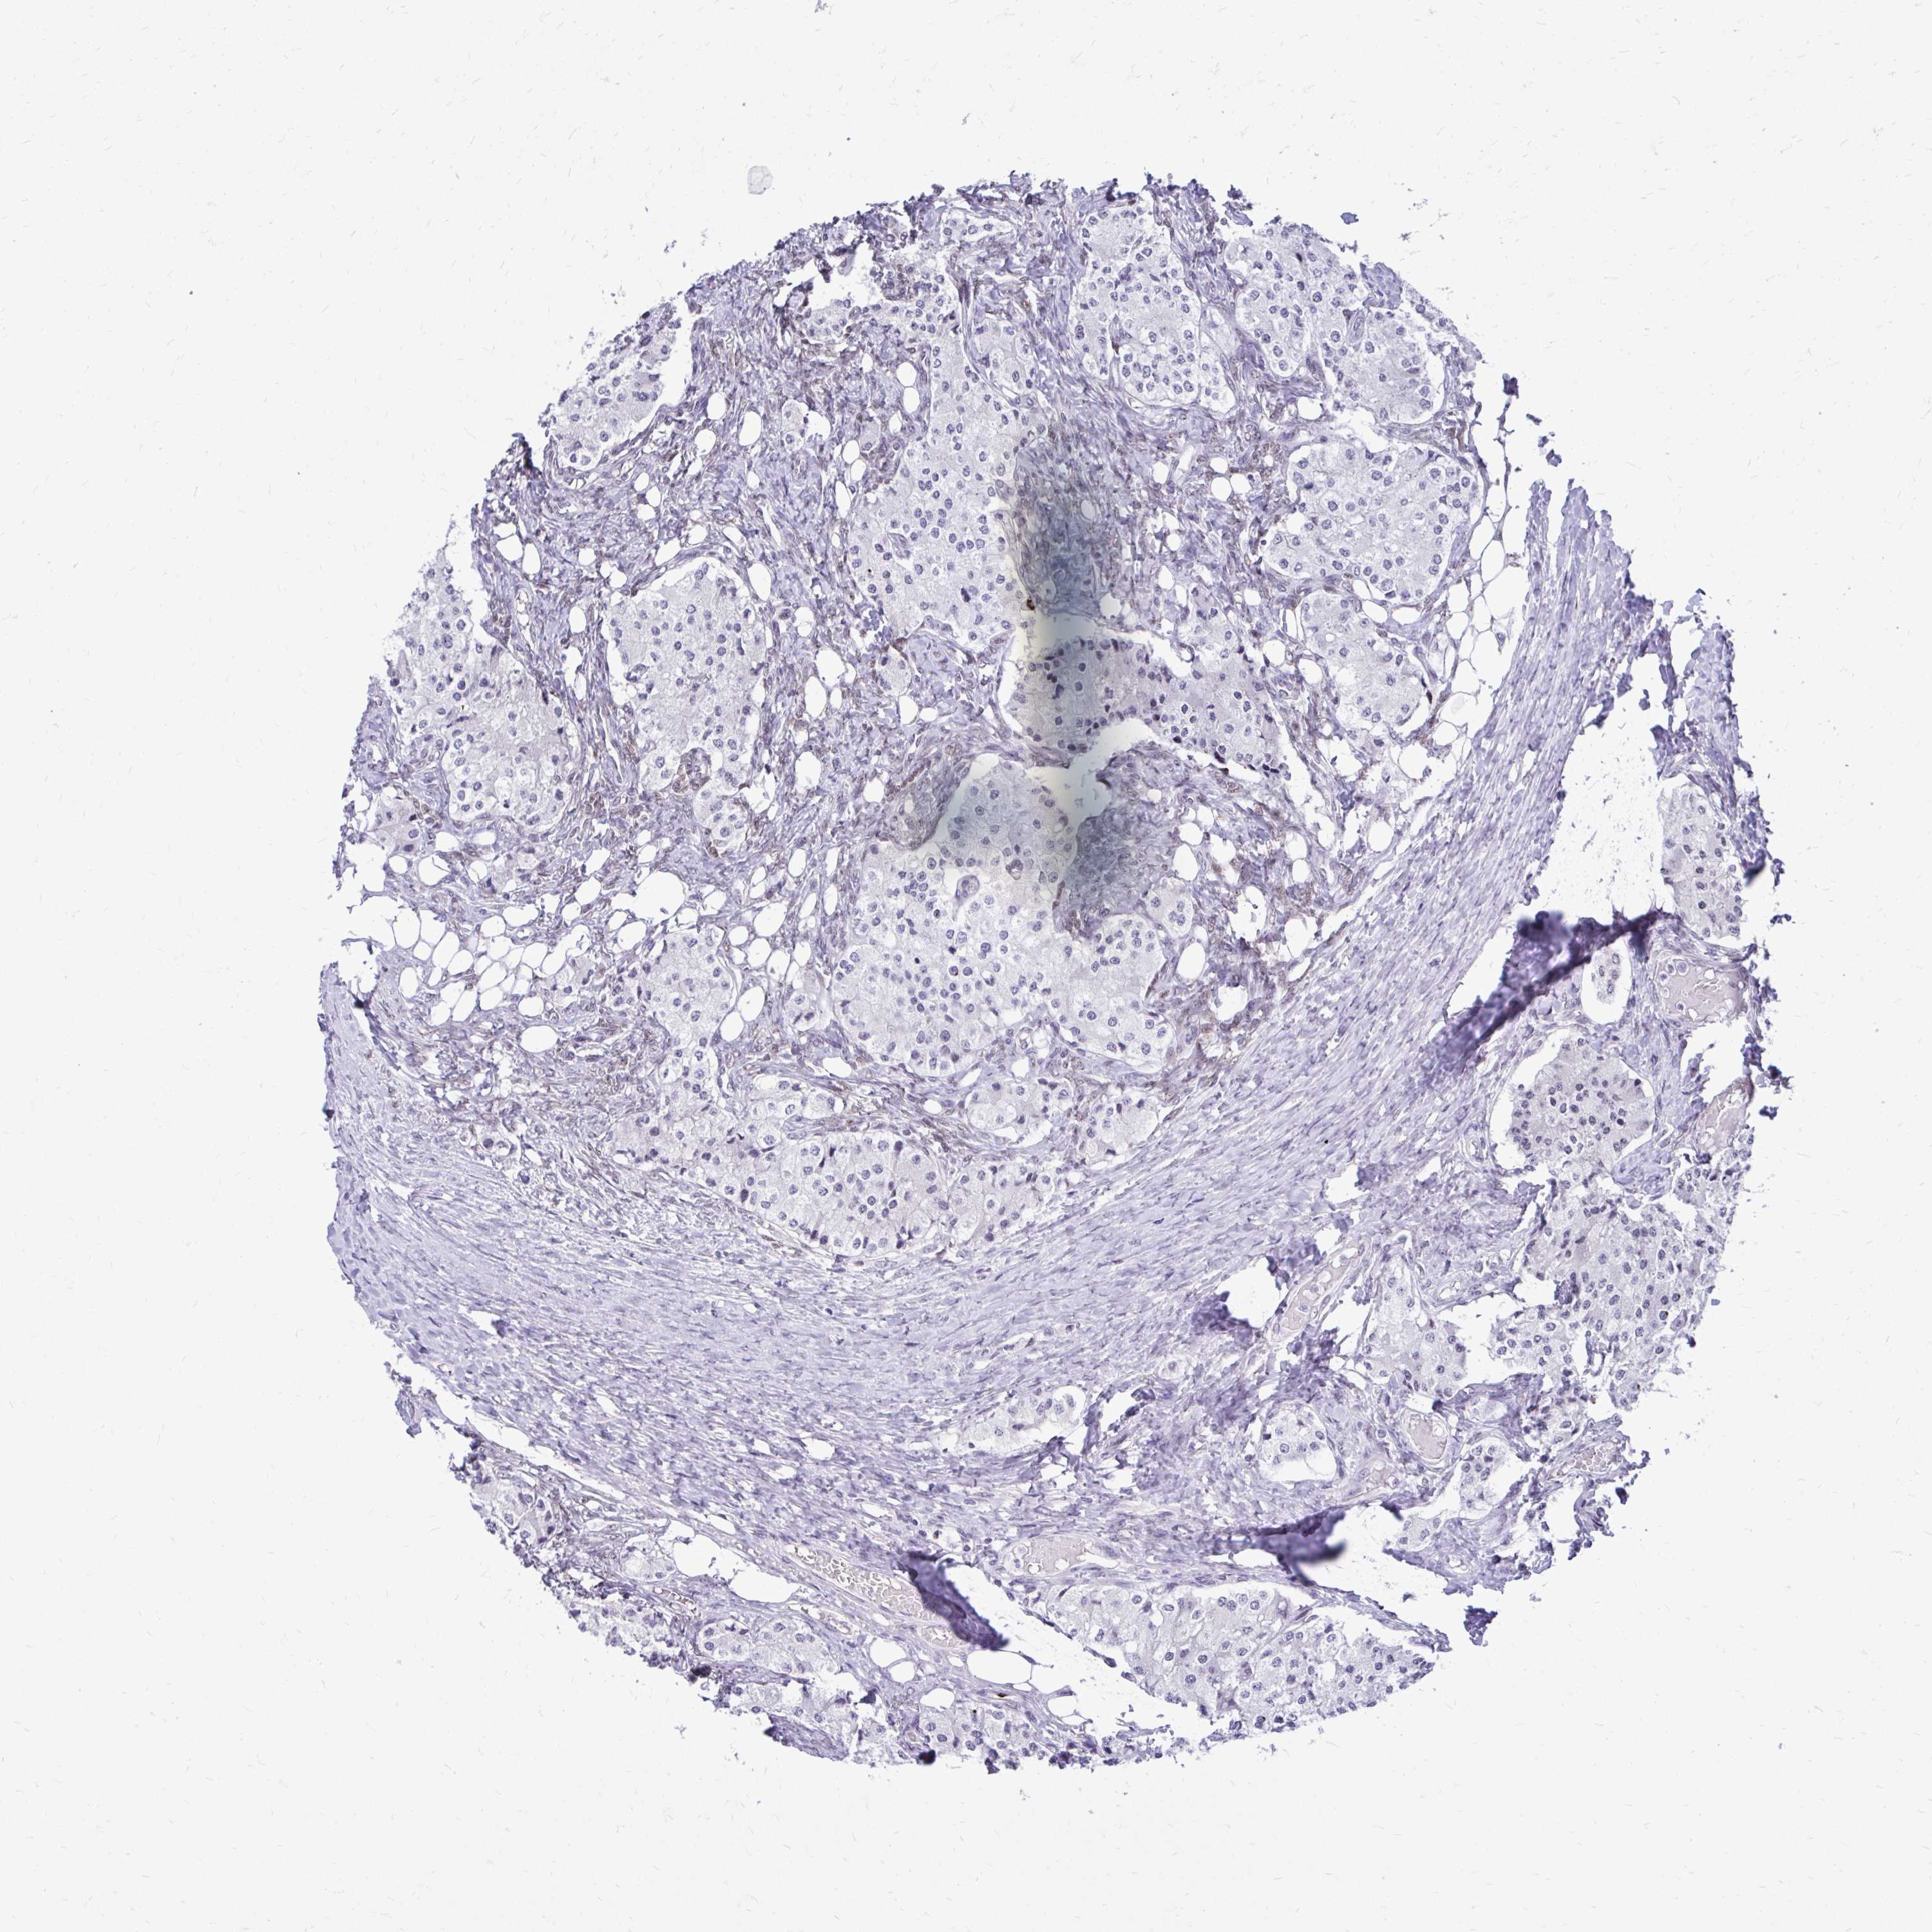

CARCINOID - Protein expressioni

A mouse-over function shows sample information and annotation data. Click on an image to view it in a full screen mode. Samples can be filtered based on level of antibody staining by selecting one or several of the following categories: high, medium, low and not detected. The assay and annotation is described here.

Antibody stainingi

Antibody staining in the annotated cell types in the current human tissue is reported as not detected, low, medium, or high, based on conventional immunohistochemistry profiling in selected tissues. This score is based on the combination of the staining intensity and fraction of stained cells.

Each image is clickable and will lead to virtual microscopy that enables deeper exploration of all samples and also displays staining intensity scores, fraction scores and subcellular localization as well as patient and tissue information for each sample.

Antibody HPA039242

Staining

High

Intensity

Strong

Quantity

>75%

Location

Nuclear

Carcinoid, malignant, NOS